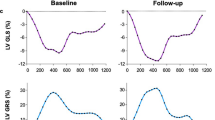

The measurements of the global circumferential strain parameters at baseline and 5 h post-shock are depicted in Table 2. While there was no change in right (RV) or left ventricular (LV) ejection fraction for either group, global peak circumferential strain worsened in both ventricles in the shock group only (LV: − 15.6 ± 3.3% to − 13.0 ± 3.6%, p < 0.01; RV: − 16.1 ± 2.3% to − 12.8 ± 4.8%, p = 0.03). Additionally, LV mechanical dispersion was increased in the shocked group post-shock (p = 0.02). Through the experiment, LV early diastolic strain rate slowed from baseline to the 5 h timepoint (1.19 ± 0.35 to 0.95 ± 0.37/s, p = 0.02) in shocked animals. No change was observed for any global strain parameters in the control group.

In a heathy swine model, serial transthoracic shocks led to a global reduction in both right and left ventricular systolic function within 5 h of the intervention assessed by circumferential strain analysis with CMR feature tracking (Fig. 6). This electrical intervention triggered the onset of regional myocardial edema in both ventricles observed by tissue characterization and increased interstitial space. We could additionally show that the extent of this injury was related to an aggravation of regional myocardial diastolic function in both ventricles. To the best of our knowledge this is the first published investigation about the onset of regional changes in systolic and diastolic biventricular function after transthoracic shocks. Previous imaging investigations have focused on global volumetric changes, while other non-invasive techniques have utilized serology markers3,6,22,23. Yet, the electrical pathway from transthoracic shocks can vary across the heart and these global techniques cannot identify the unique distributions of myocardial injury that occur as a result. The development of feature tracking analysis to quantify regional strain allowed us to colocalize the myocardial dysfunction with acute changes in myocardial tissue injury providing a more sensitive assessment of acute myocardial caused by electrical interventions.